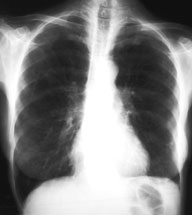

Eine 70-jährige Patientin meldet sich bei Ihnen in der Praxis mit Verschlechterung des Allgemeinzustandes seit 4-5 Wochen und Fieber bis maximal 38.5 Grad.

Des weitern klagt sie über einen trockenen Husten. Ausser einer arteriellen Hypertonie besteht als Vorerkrankung eine leichte COPD. Da Sie ausser dem Husten keinen klinischen Fokus für einen Infekt finden, entschliessen Sie sich für ein Thorax-Bild. Optimalerweise haben Sie sogar noch ein pa-Thorax von vor 2 Jahren zum Vergleich:

Thorax pa aktuell

Thorax pa vor 2 Jahren